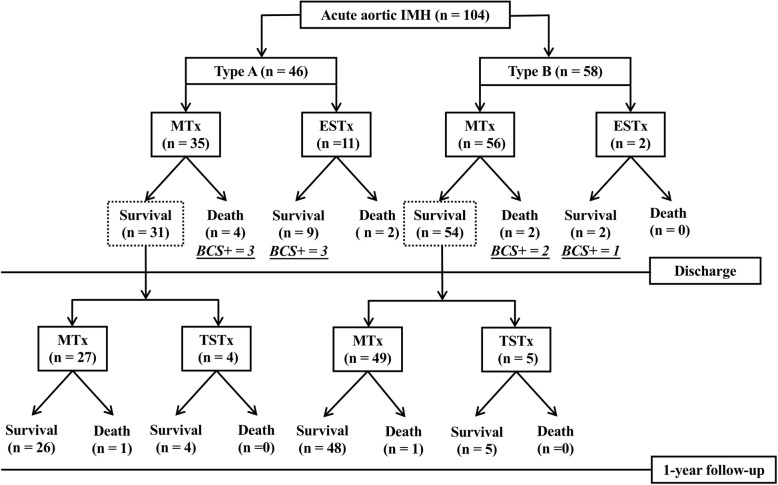

In-hospital mortality and 1-year mortality of aortic IMH

The treatment methods and clinical outcomes of 104 patients with acute aortic IMH are summarized in Fig. 1. Thirty-five of 46 patients (76.1%) with type A and 56 of 58 patients (96.6%) with type B, uncomplicated IMH received initial medical treatment; the in-hospital mortalities were 11.4% (4/35 patients) and 3.4% (2/58 patients), respectively. Thirteen patients with complicated IMH, managed with early surgical or endovascular treatment, had in-hospital mortalities of 18.2% (2/11 patients) in type A and 0% (0/2 patients) in type B IMH, respectively. Overall in-hospital mortality was 7.7% (8/104 patients).

Fig. 1.

Selected treatment and outcomes of 118 patients with acute aortic IMH. MTx = medical treatment, ESTx = early surgical or endovascular treatment, BCS+ = positive broken-crescent sign on CT, TSTx = timely surgical or endovascular treatment

Among 85 patients with medical treatment and uneventful discharges, four type A (12.9%, 4/31 patients) and five type B IMH (9.3%, 5/54 patients) showed progression to aortic dissection or dilatation, development of ULP, or persistent chest or back pain in follow-up and underwent subsequent surgical or endovascular treatment. Of these 85 patients, death occurred in one type A (3.7%, 1/27 patients) and one type B (2.0%, 1/49 patients) IMH patient with medical treatment. With the adoption of a wait-and-watch strategy for initially uncomplicated aortic IMH, 1-year mortalities after medical treatment and timely surgery were 14.3% (5/35 patients) in patients with type A and 5.4% (3/56 patients) in patients with type B IMH with an overall mortality of 9.6% (10/104 patients).